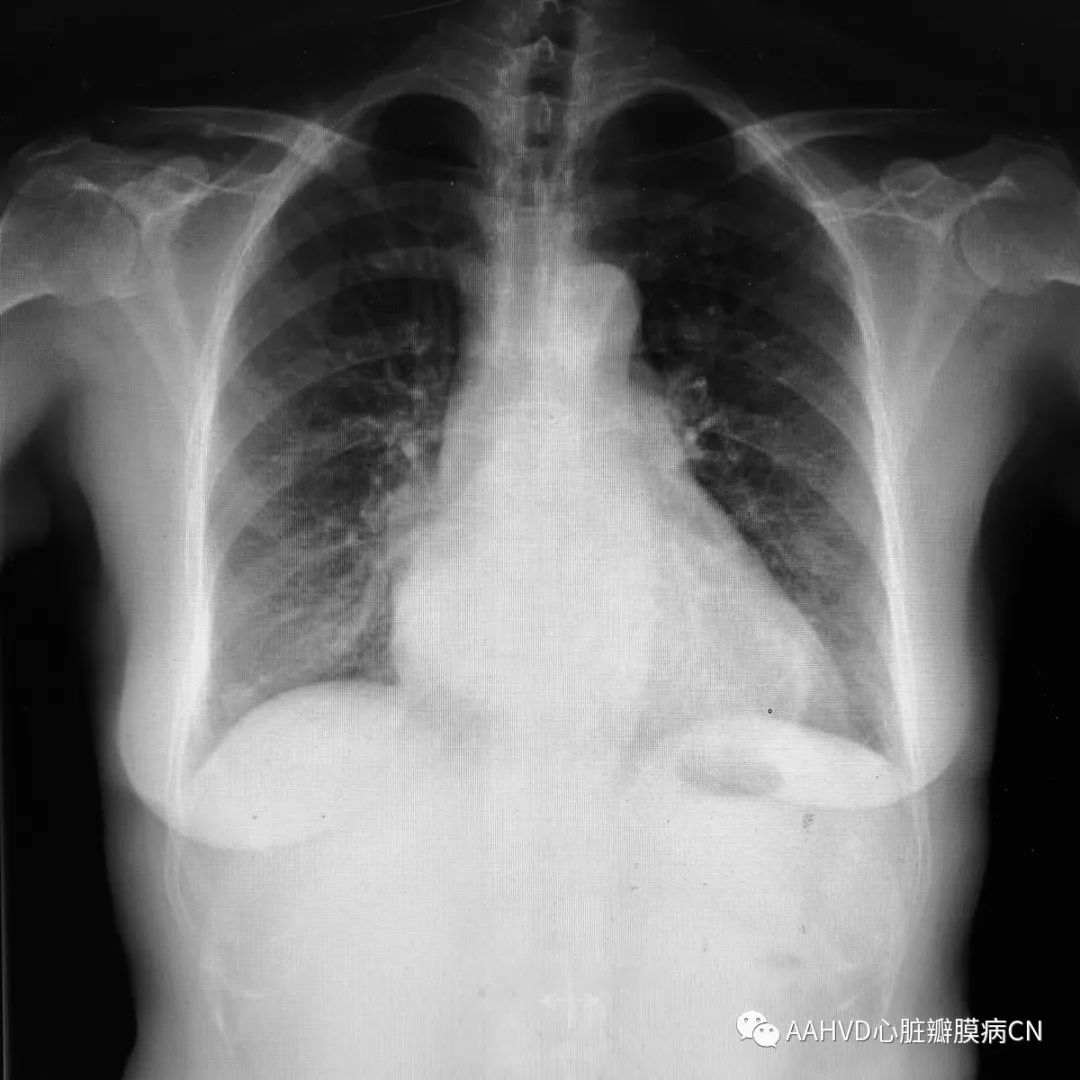

术前胸片

640_7

术前经胸超声:

风湿性瓣膜病改变不除外,二尖瓣返流面积12.7cm²(重度返流),瓣口面积1.9cm²(轻度狭窄),E前向流速296cm/s;三尖瓣返流面积7.5cm²(中量返流)。